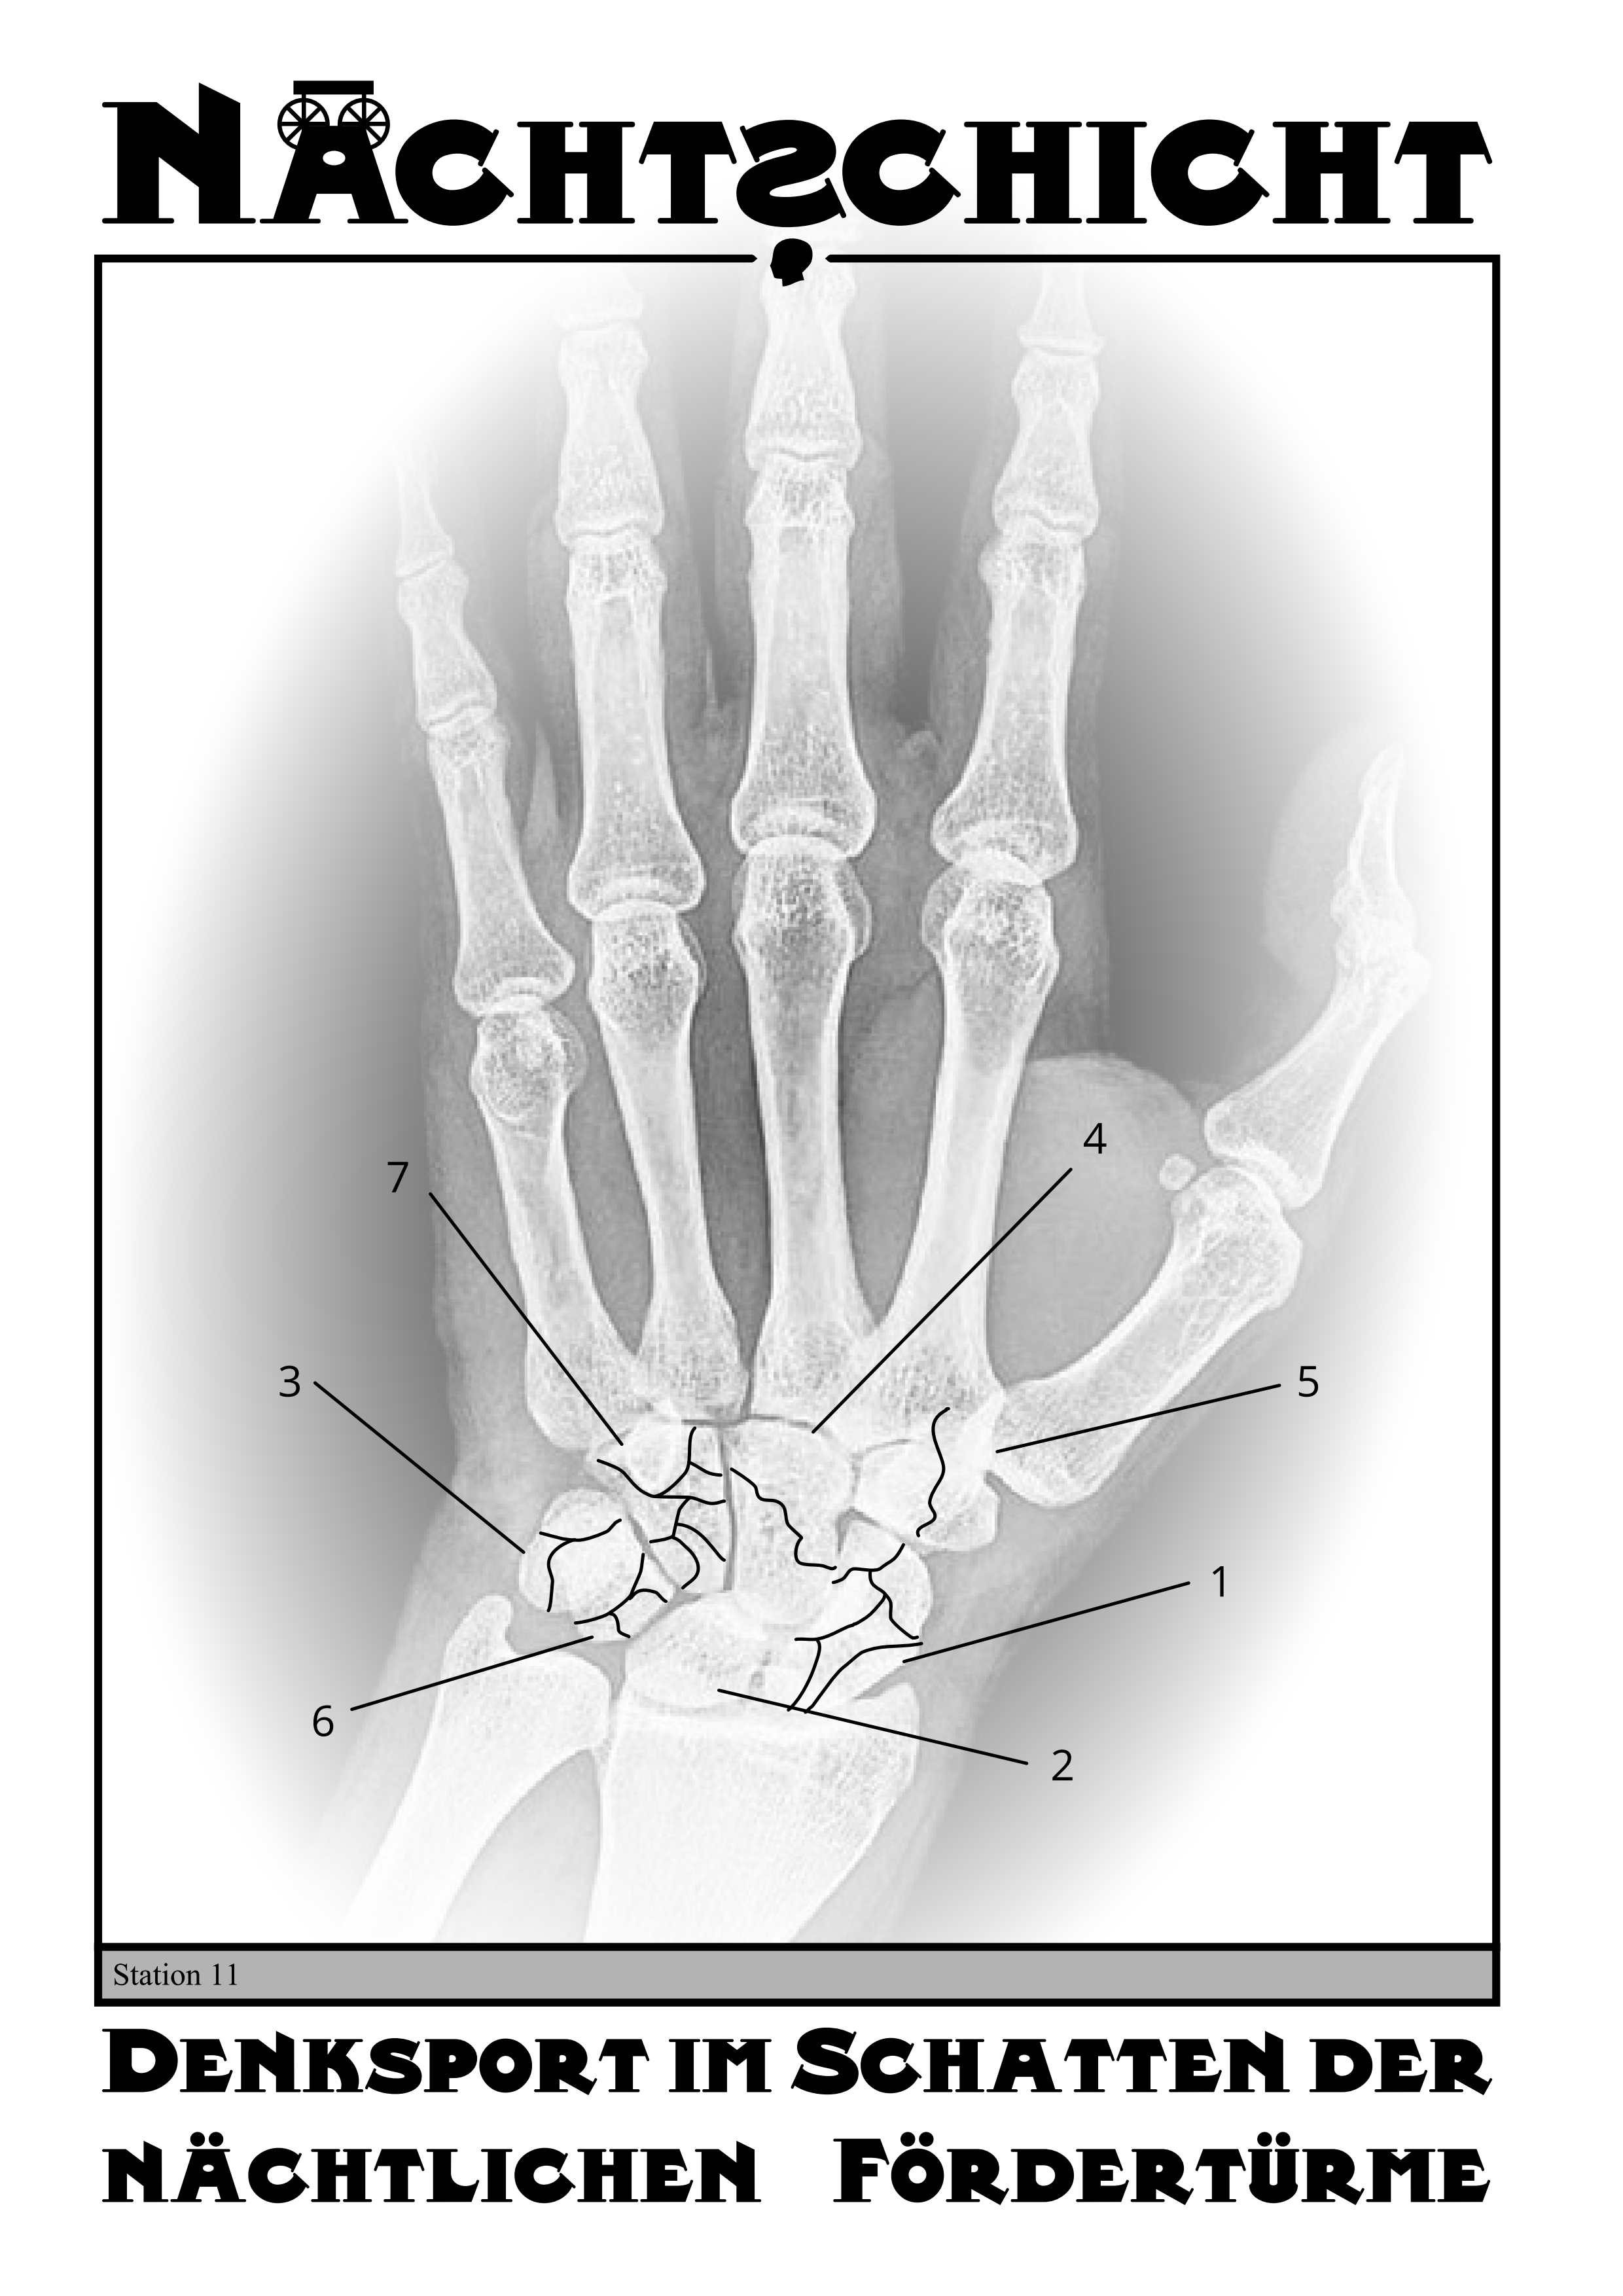

Station 11 - Trümmerbruch

Deutsche Knochennamen der Hand durch Onlinerecherche finden.

Anzahl der Brüche des Knochen gibt an, welcher Buchstaben des Knochen genommen werden muss.

Buchstaben in der Reihenfolge der Knochennummer sortieren, um das Lösungswort zu erhalten.